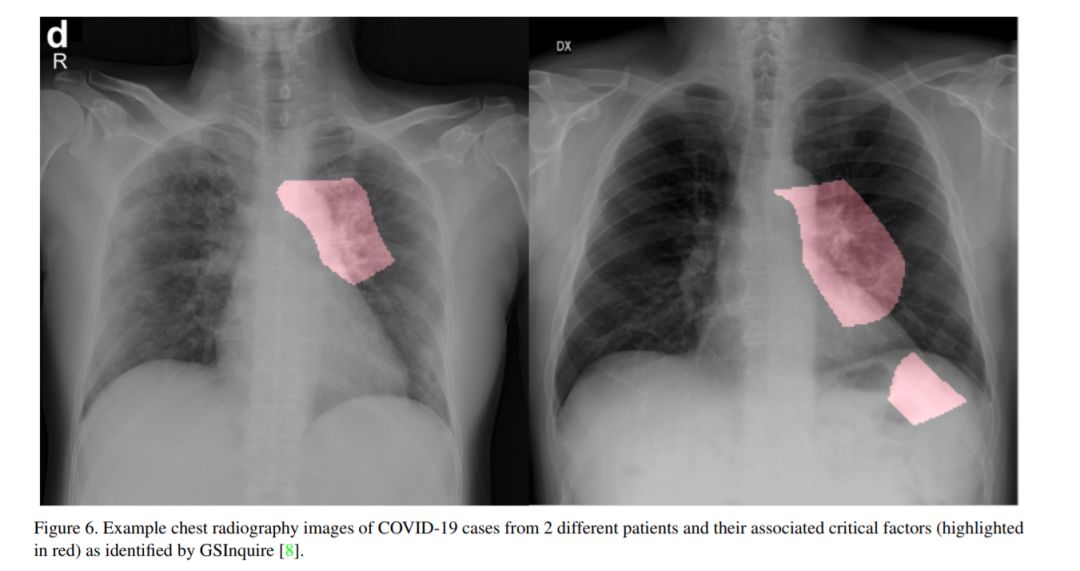

图1: 样本COVIDx数据集上的前后胸片图像:(a)细菌感染、(b)非COVID-19病毒感染和(c)COVID-19病毒感染。

COVID-19大流行继续对全球人口的健康和福祉产生破坏性影响。与COVID-19作斗争的一个关键步骤是对受感染患者进行有效的筛查,其中最关键的筛查方法之一是使用胸片进行放射成像。基于此,许多基于深度学习的人工智能(AI)系统被提出,结果显示在使用胸片图像检测COVID-19感染患者的准确性方面很有希望。然而,据作者所知,这些开发的人工智能系统是封闭的,研究社区无法对其进行更深入的理解和扩展,也无法对公众进行访问和使用。因此,在本研究中,我们引入COVID-Net,这是一种针对胸片图像中COVID-19的检测而设计的深度卷积神经网络,它是开源的,并且对公众开放。我们还描述了用于训练COVID-Net的胸片数据集,我们将其称为COVIDx,它由来自两个开放访问数据库的2839例患者的5941张前后胸片图像组成。此外,我们研究COVID- net如何使用可解释性方法进行预测,以获得与COVID病例相关的关键因素的更深入的了解,从而帮助临床医生改进筛选。决不生产就绪的解决方案,希望开放获取COVID-Net,随着描述构建开源COVIDx数据集,将杠杆,建立由研究人员和公民数据科学家们还都加快发展的高度准确的实际深度学习解决方案检测COVID-19病例和加速处理那些最需要的人。

基于迫切需要开发解决方案以帮助抗击COvID-19大流行,并受到研究社区开源和开放获取努力的启发,本研究引入COVID-Net,这是一种深度卷积神经网络设计,专门用于从公开的、向公众开放的胸片图像中检测COvID-19病例。我们还描述了用于训练COVID-Net的数据集,我们将其称为COVIDx,它由来自2839例患者的5941张前后胸片图像组成,是由包含胸片图像的两个开放访问数据库(即科恩(Cohen)和卡格尔(kaggle))。此外,我们研究COVID- net如何使用可解释性方法进行预测,以获得与COVID病例相关的关键因素的更深入的了解,从而帮助临床医生改进筛选。